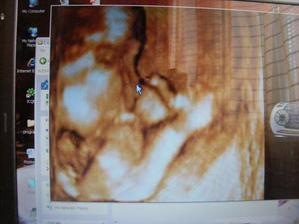

lubkaaa

24. mar 2009

2.miminko